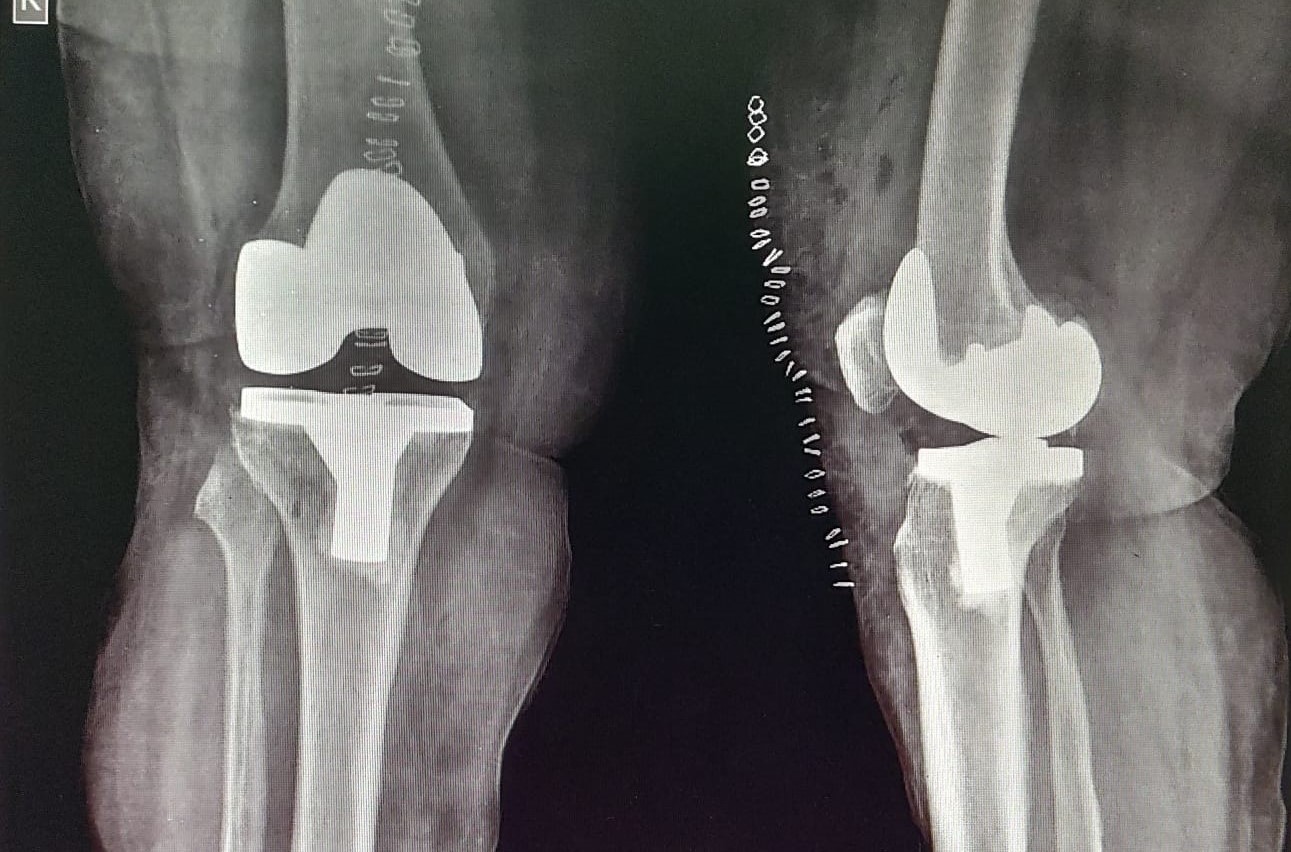

Knee and Hip Replacement